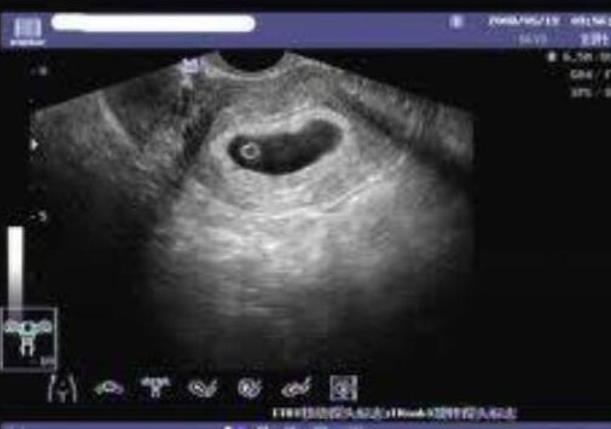

云南省第一人民医院三代成功率 云南做供卵试管最受欢迎医院排名 ‘b超写的哪句有可能是男孩’